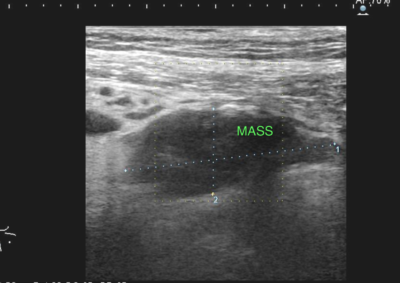

腫瘍外科 注意 ボタンをクリックした先に、治療中および手術中の画像が説明で使用されている場合がございます。 そのような画像に弱い方は閲覧なさらないようお願いいたします。 腫瘍外科 犬の甲状腺癌 軟部組織外科腫瘍外科 唾液腺癌 Salivary gland carcinoma 軟部組織外科腫瘍外科 胃部分切除術・ビルロートI 腫瘍外科 MLO 多小葉性骨腫瘍 腫瘍外科 軟部組織肉腫 G3 軟部組織外科腫瘍外科 直腸プルスルー 内科腫瘍外科 尾状葉乳頭突起に限局した高分化型肝細胞癌 内科腫瘍外科 猫の消化管型リンパ腫(腸穿孔を伴う) 腫瘍外科救急・集中治療 腹腔内出血 内科腫瘍外科救急・集中治療 細菌性腹膜炎 腫瘍外科 肝臓原発血管肉腫 腫瘍外科 犬の原発生肺癌(左) <1234567> 症例カテゴリー 放射線治療整形外科軟部組織外科脳神経外科内科腫瘍外科救急・集中治療リハビリテーション科腫瘍内科内視鏡科脳神経科呼吸器外科中医・漢方猫の腎移植循環器科